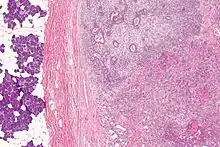

Micrograph of a carcinoma ex pleomorphic adenoma. The carcinoma component is on the lower right of the image. Benign parotid gland is seen at the left and pleomorphic adenoma is seen at the upper right. H&E stain.

Carcinoma ex pleomorphic adenoma (ca ex PA) is a type of cancer typically found in the parotid gland. It arises from the benign tumour pleomorphic adenoma.